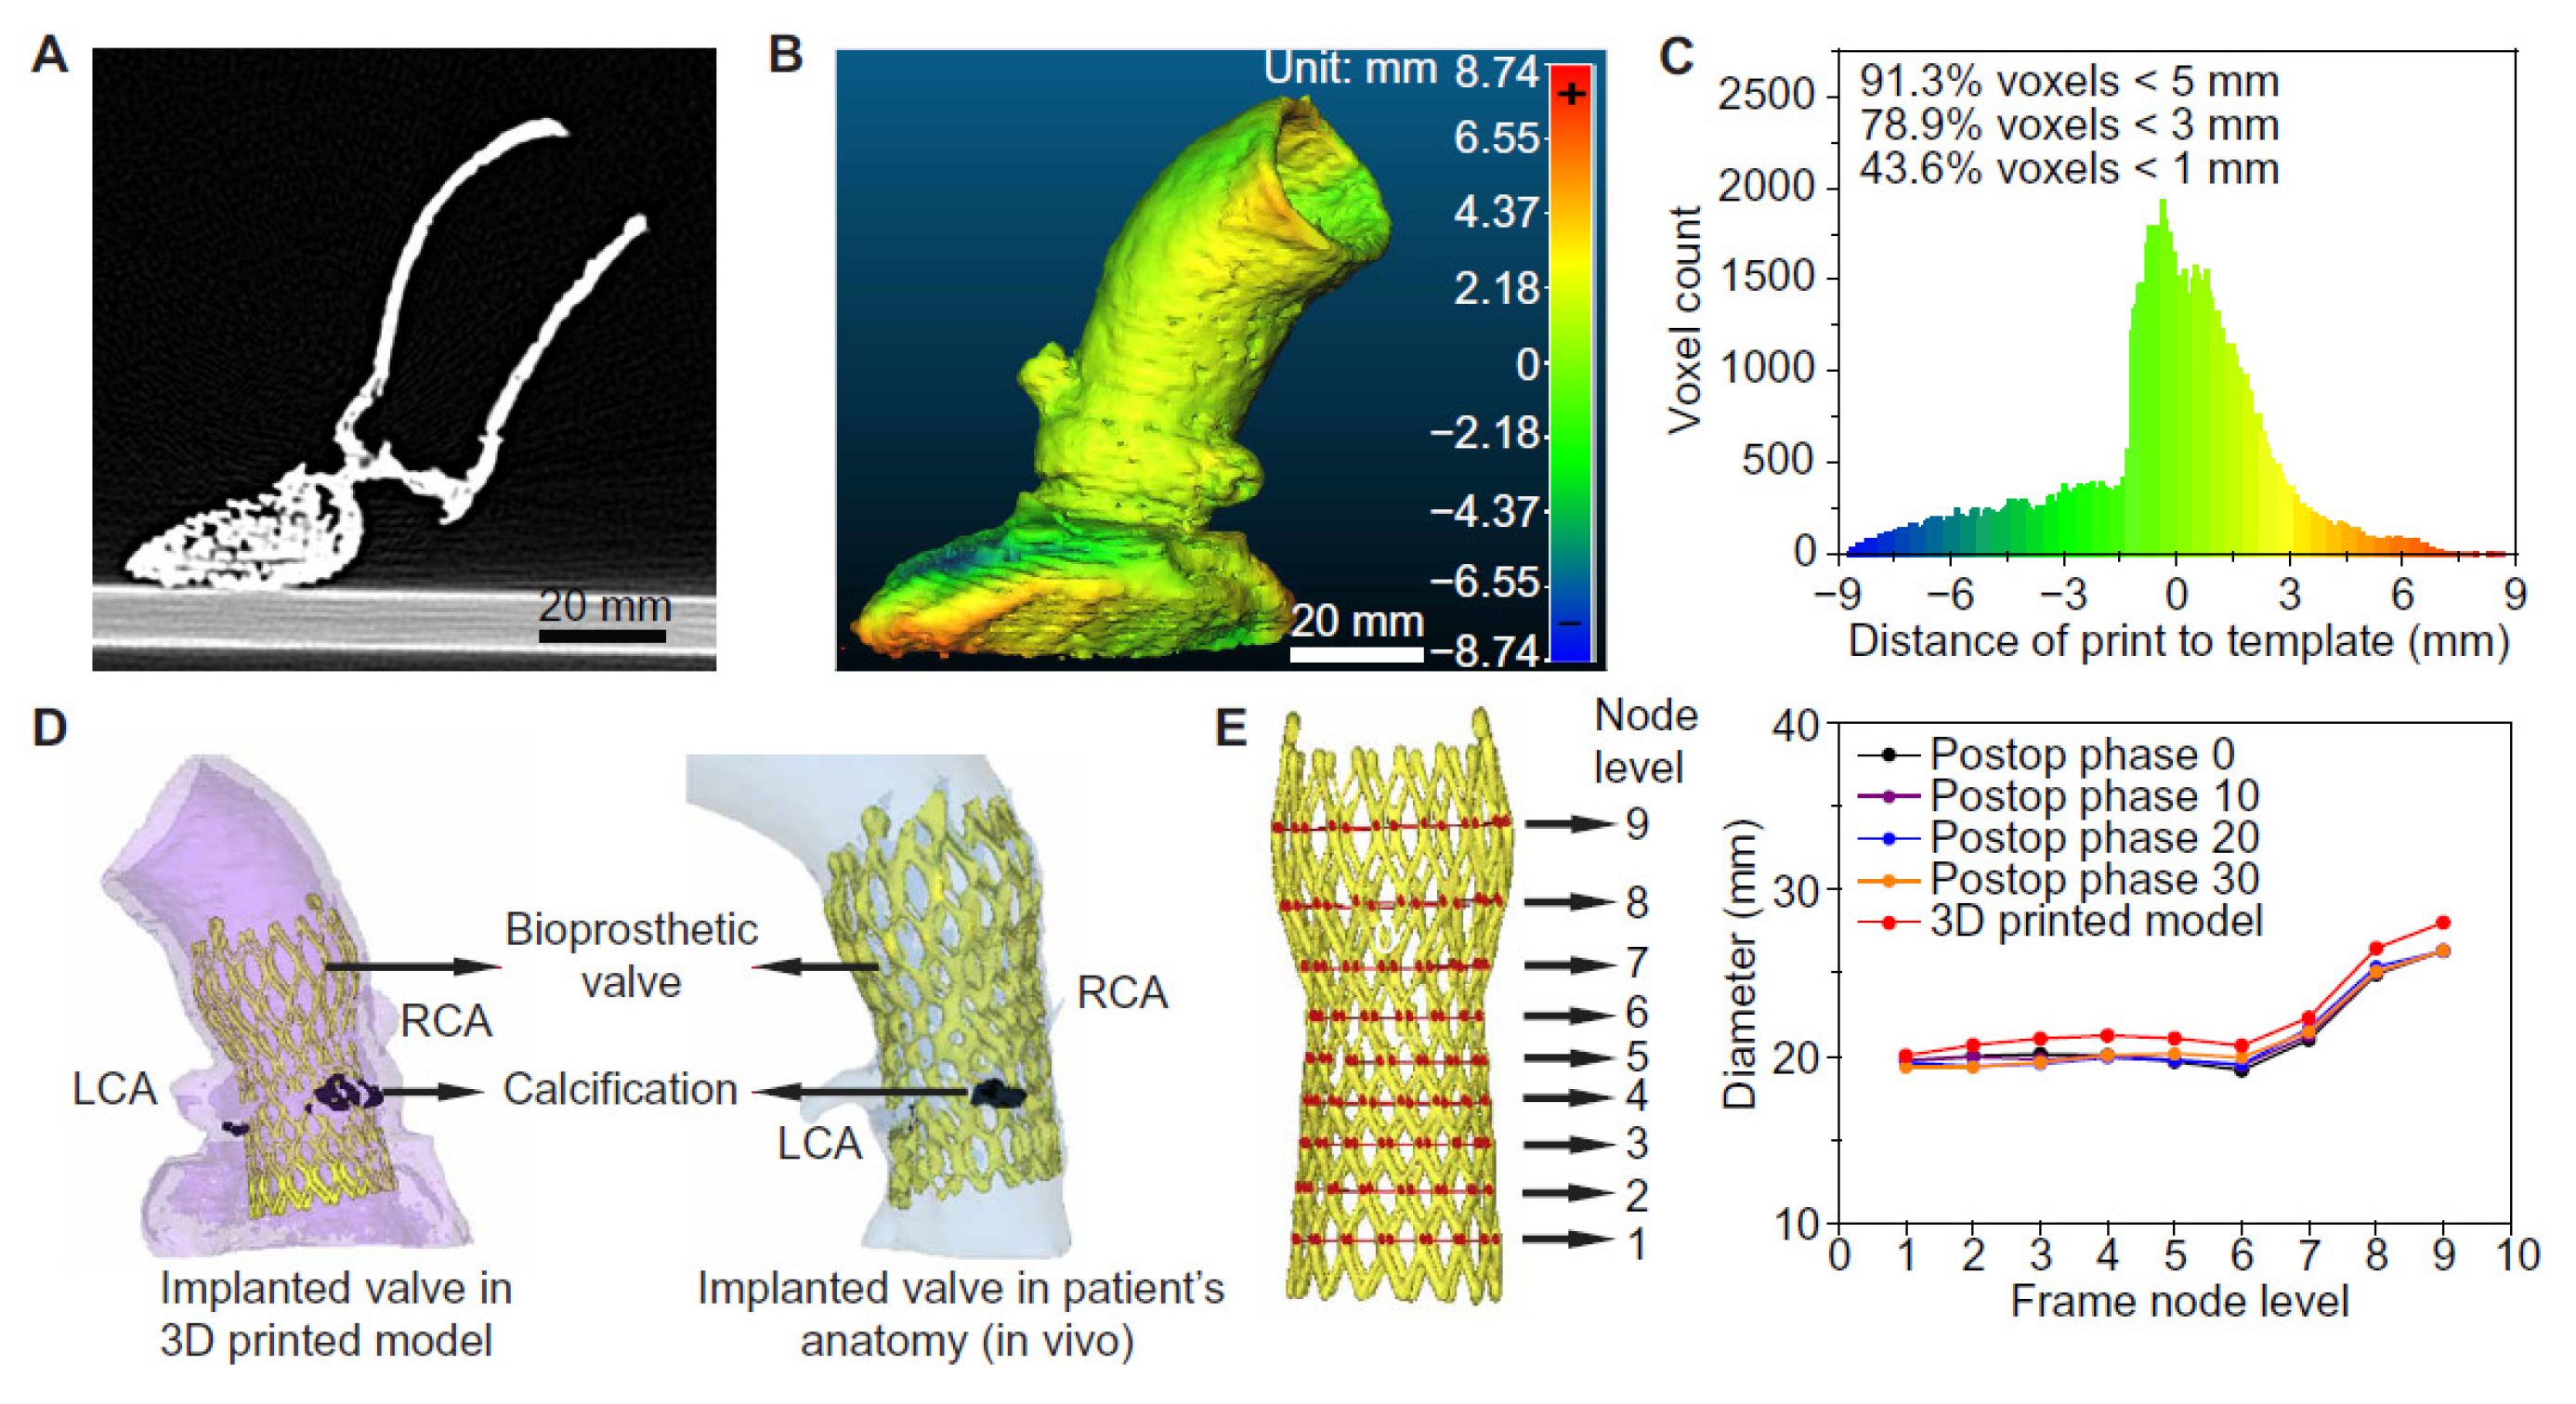

2. Steps to Create 3D Segmentation Volume Data for 3D Printing

3. Clinical Applications of 3D Printing in Cardiovascular Disease

3.1. 3D Printing in Congenital Heart Disease

3.2. 3D Printing in Structural Heart Disease and Cardiac Interventions

3.3. 3D Printing in Coronary Artery Disease

3.4. 3D Printing in Aortic Aneurysm and Aortic Dissection

3.5. 3D Printing in Pulmonary Artery Disease

3.6. 3D Bioprinting in Cardiovascular Disease